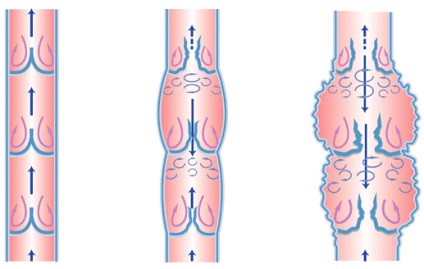

Normális esetben a vér feljebb a vénákban a szív felé. Ahhoz, hogy a vér nem a gravitáció miatt leeshet, vannak szelepek a vénákban az alsó végtagok. Szelep - egy „eszköz” megakadályozza, hogy a visszatérő vér áramlását. Szelepek a vénákban az alsó végtagok vannak elrendezve teljes hossza mentén a hajó. Ennek eredményeként, visszértágulat szelepek már nem késlelteti a vér, és irányítja az ellenkező irányban a szívből. Az eredmény stagnálása erek az alsó végtagok, következésképpen expandált Bécs, megvastagszik, és láthatóvá válik.